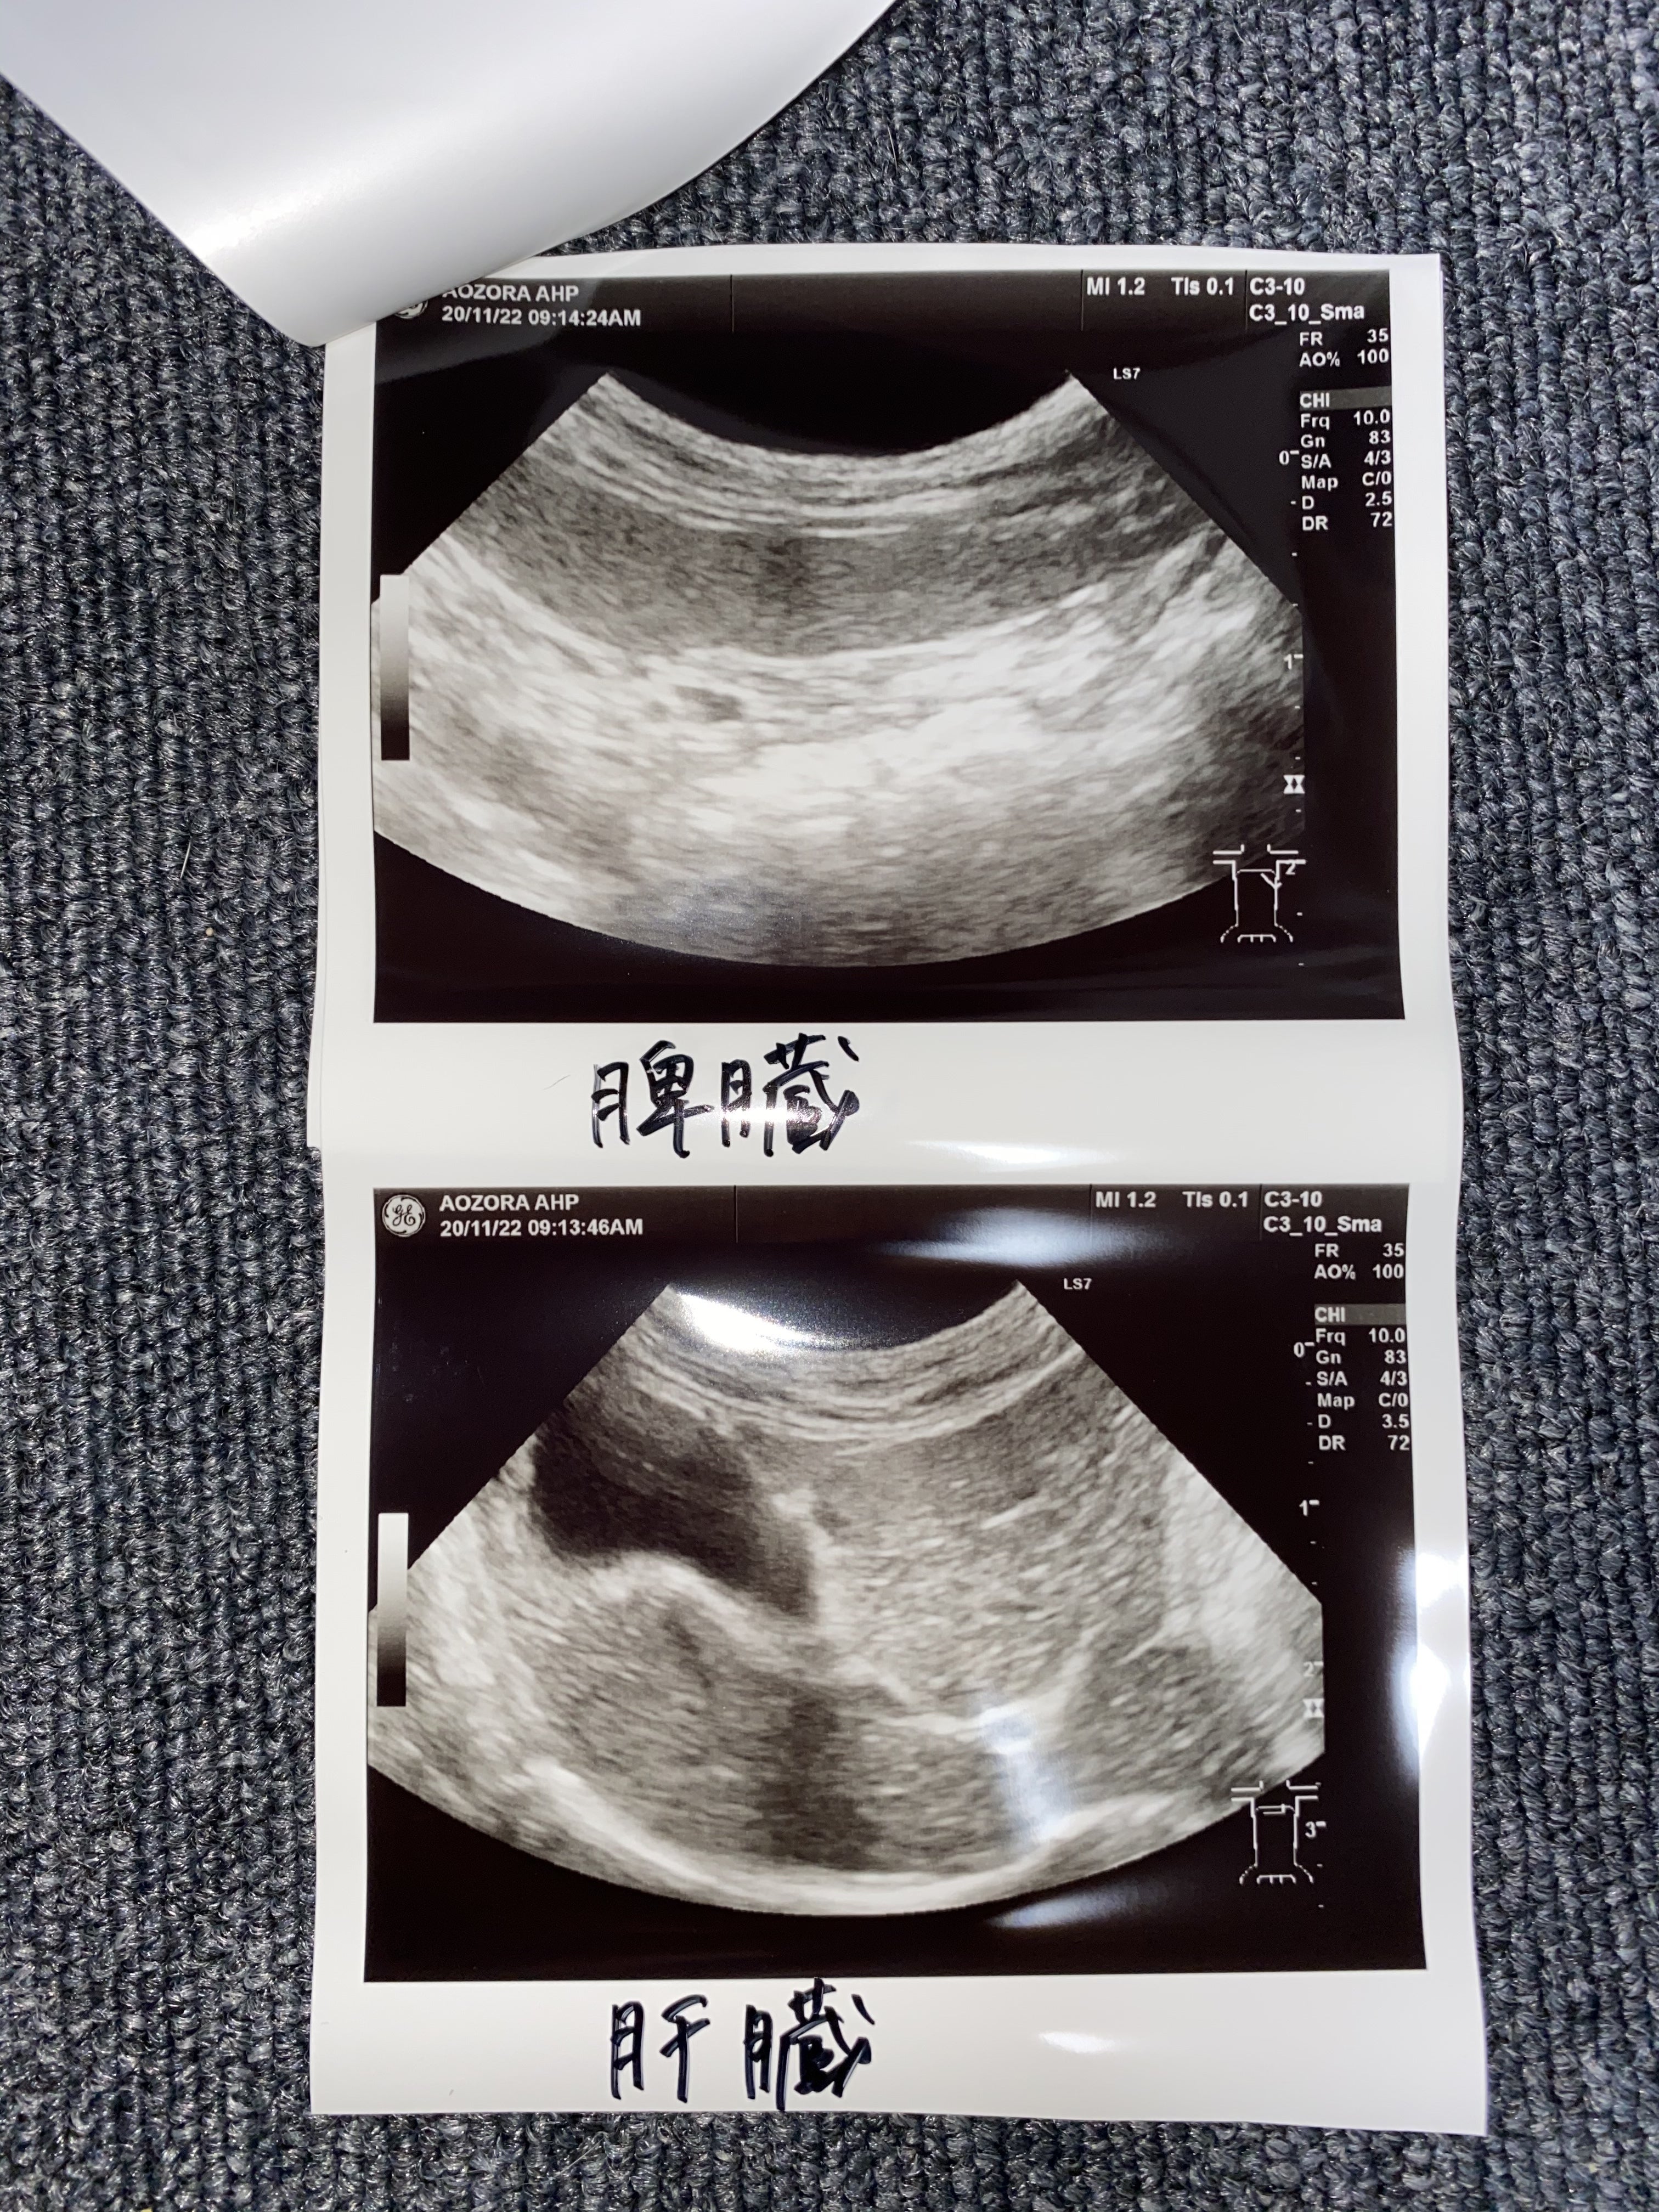

エコー検査も綺麗で問題ないそうです。